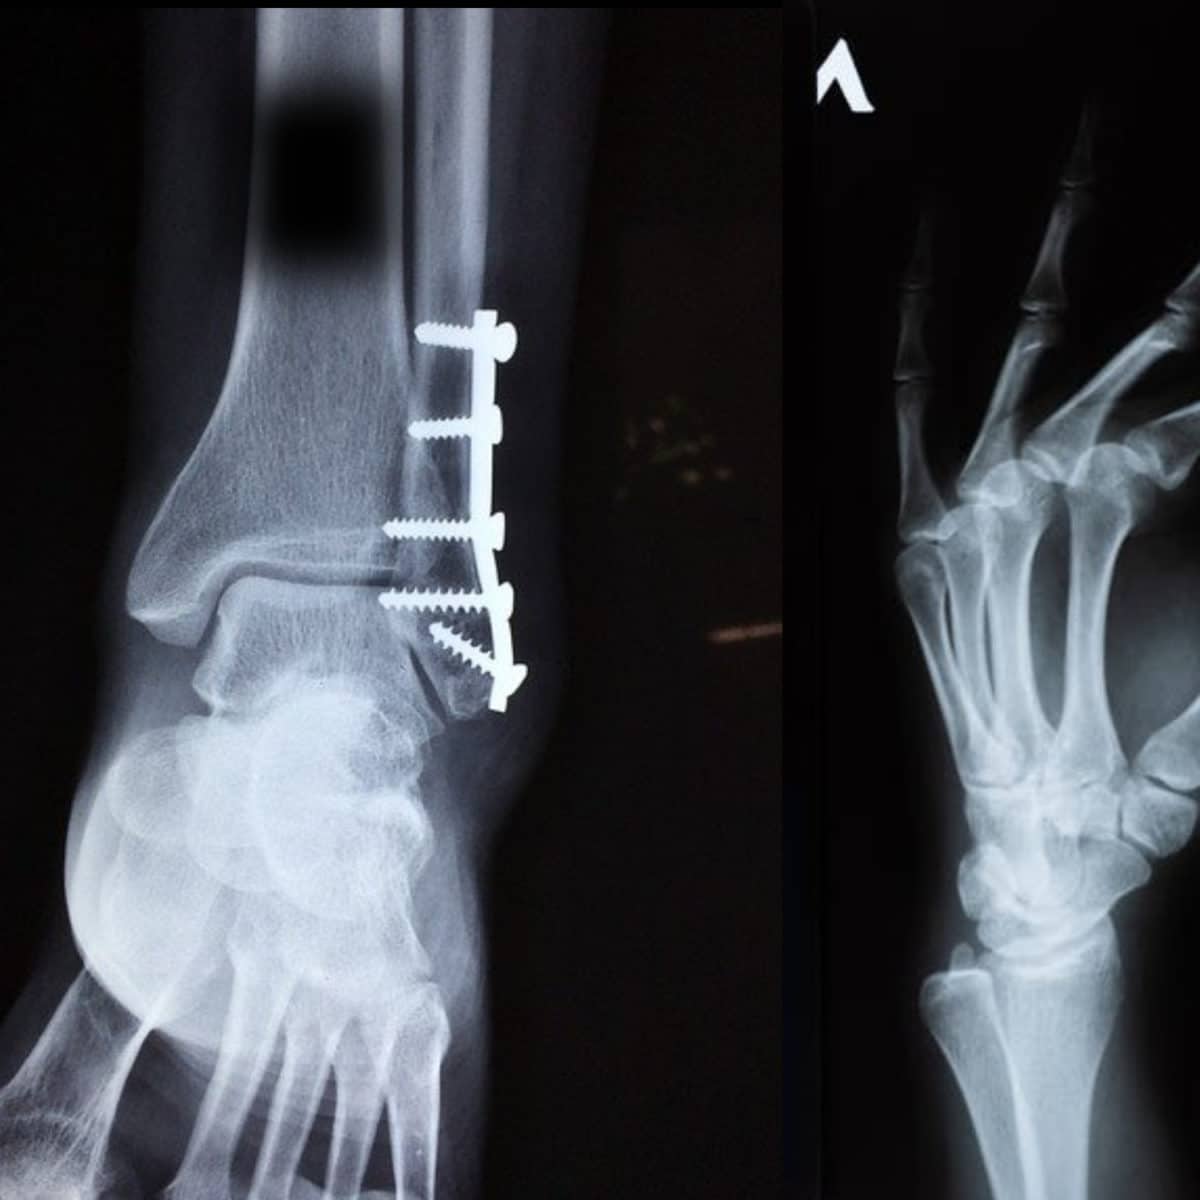

Two types of fracture surgeries exist: Open Reduction and Internal Fixation (ORIF) and External Fixation.

Open Reduction and Internal Fixation (ORIF)

This is a surgery in which the fracture site is adequately exposed and the reduction of the fracture is done. This fracture surgery is completed with devices such as Kirschner wires, screws and plates, and intramedullary nails.